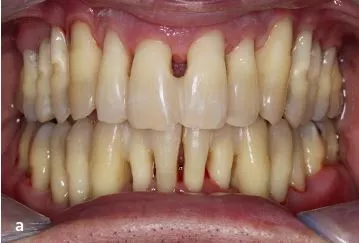

Der Patient (männlich, 48 Jahre alt) wurde im Jahr 2018 mit Verdacht auf aggressive Parodontitis (alte Nomenklatur) ins ZFZ Stuttgart überwiesen. Es bestanden keine Vorerkrankungen, keine familiären Auffälligkeiten und der Patient war Nichtraucher. Die Diagnose des überweisenden Zahnarztes konnte bestätigt werden.

Folgende klinische Befunde wurden eingangs erhoben: Plaqueindex (Ausgangssituation: QH 54%), Blutungsindex (Ausgangssituation: BOP 72%), Sondierungstiefen (Ausgangssituation: bis zu 10 mm – aus diesem Grund erfolgte eine teilweise Schienung) (Abb. 1).

Ein Jahr nach Abschluss der aktiven Phase zeichnet sich eine positive Entwicklung ab. Die Sondierungstiefen sind deutlich reduziert (< 7 mm); deutliche Verbesserungen wurden bezüglich der Blutung (BOP 35%) und der Belagsbildung (QH 27%) registriert (Abb. 2a–c).